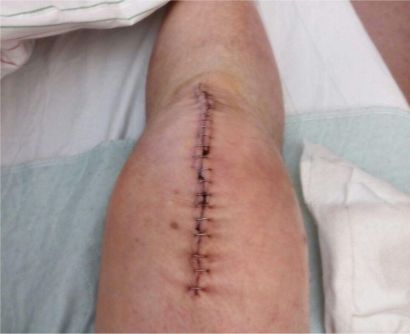

Noch während des Krankenhausaufenthaltes wurde ich einzeln und in der Gruppe physiotherapeutisch betreut (u.a. auch durch Wassergymnastik). Weniger appetitlich sah dann die über 15 cm lange Wunde aus, die mit Klammern zusammengefügt wurde.

geklammerte Wunde nach Knie-OP